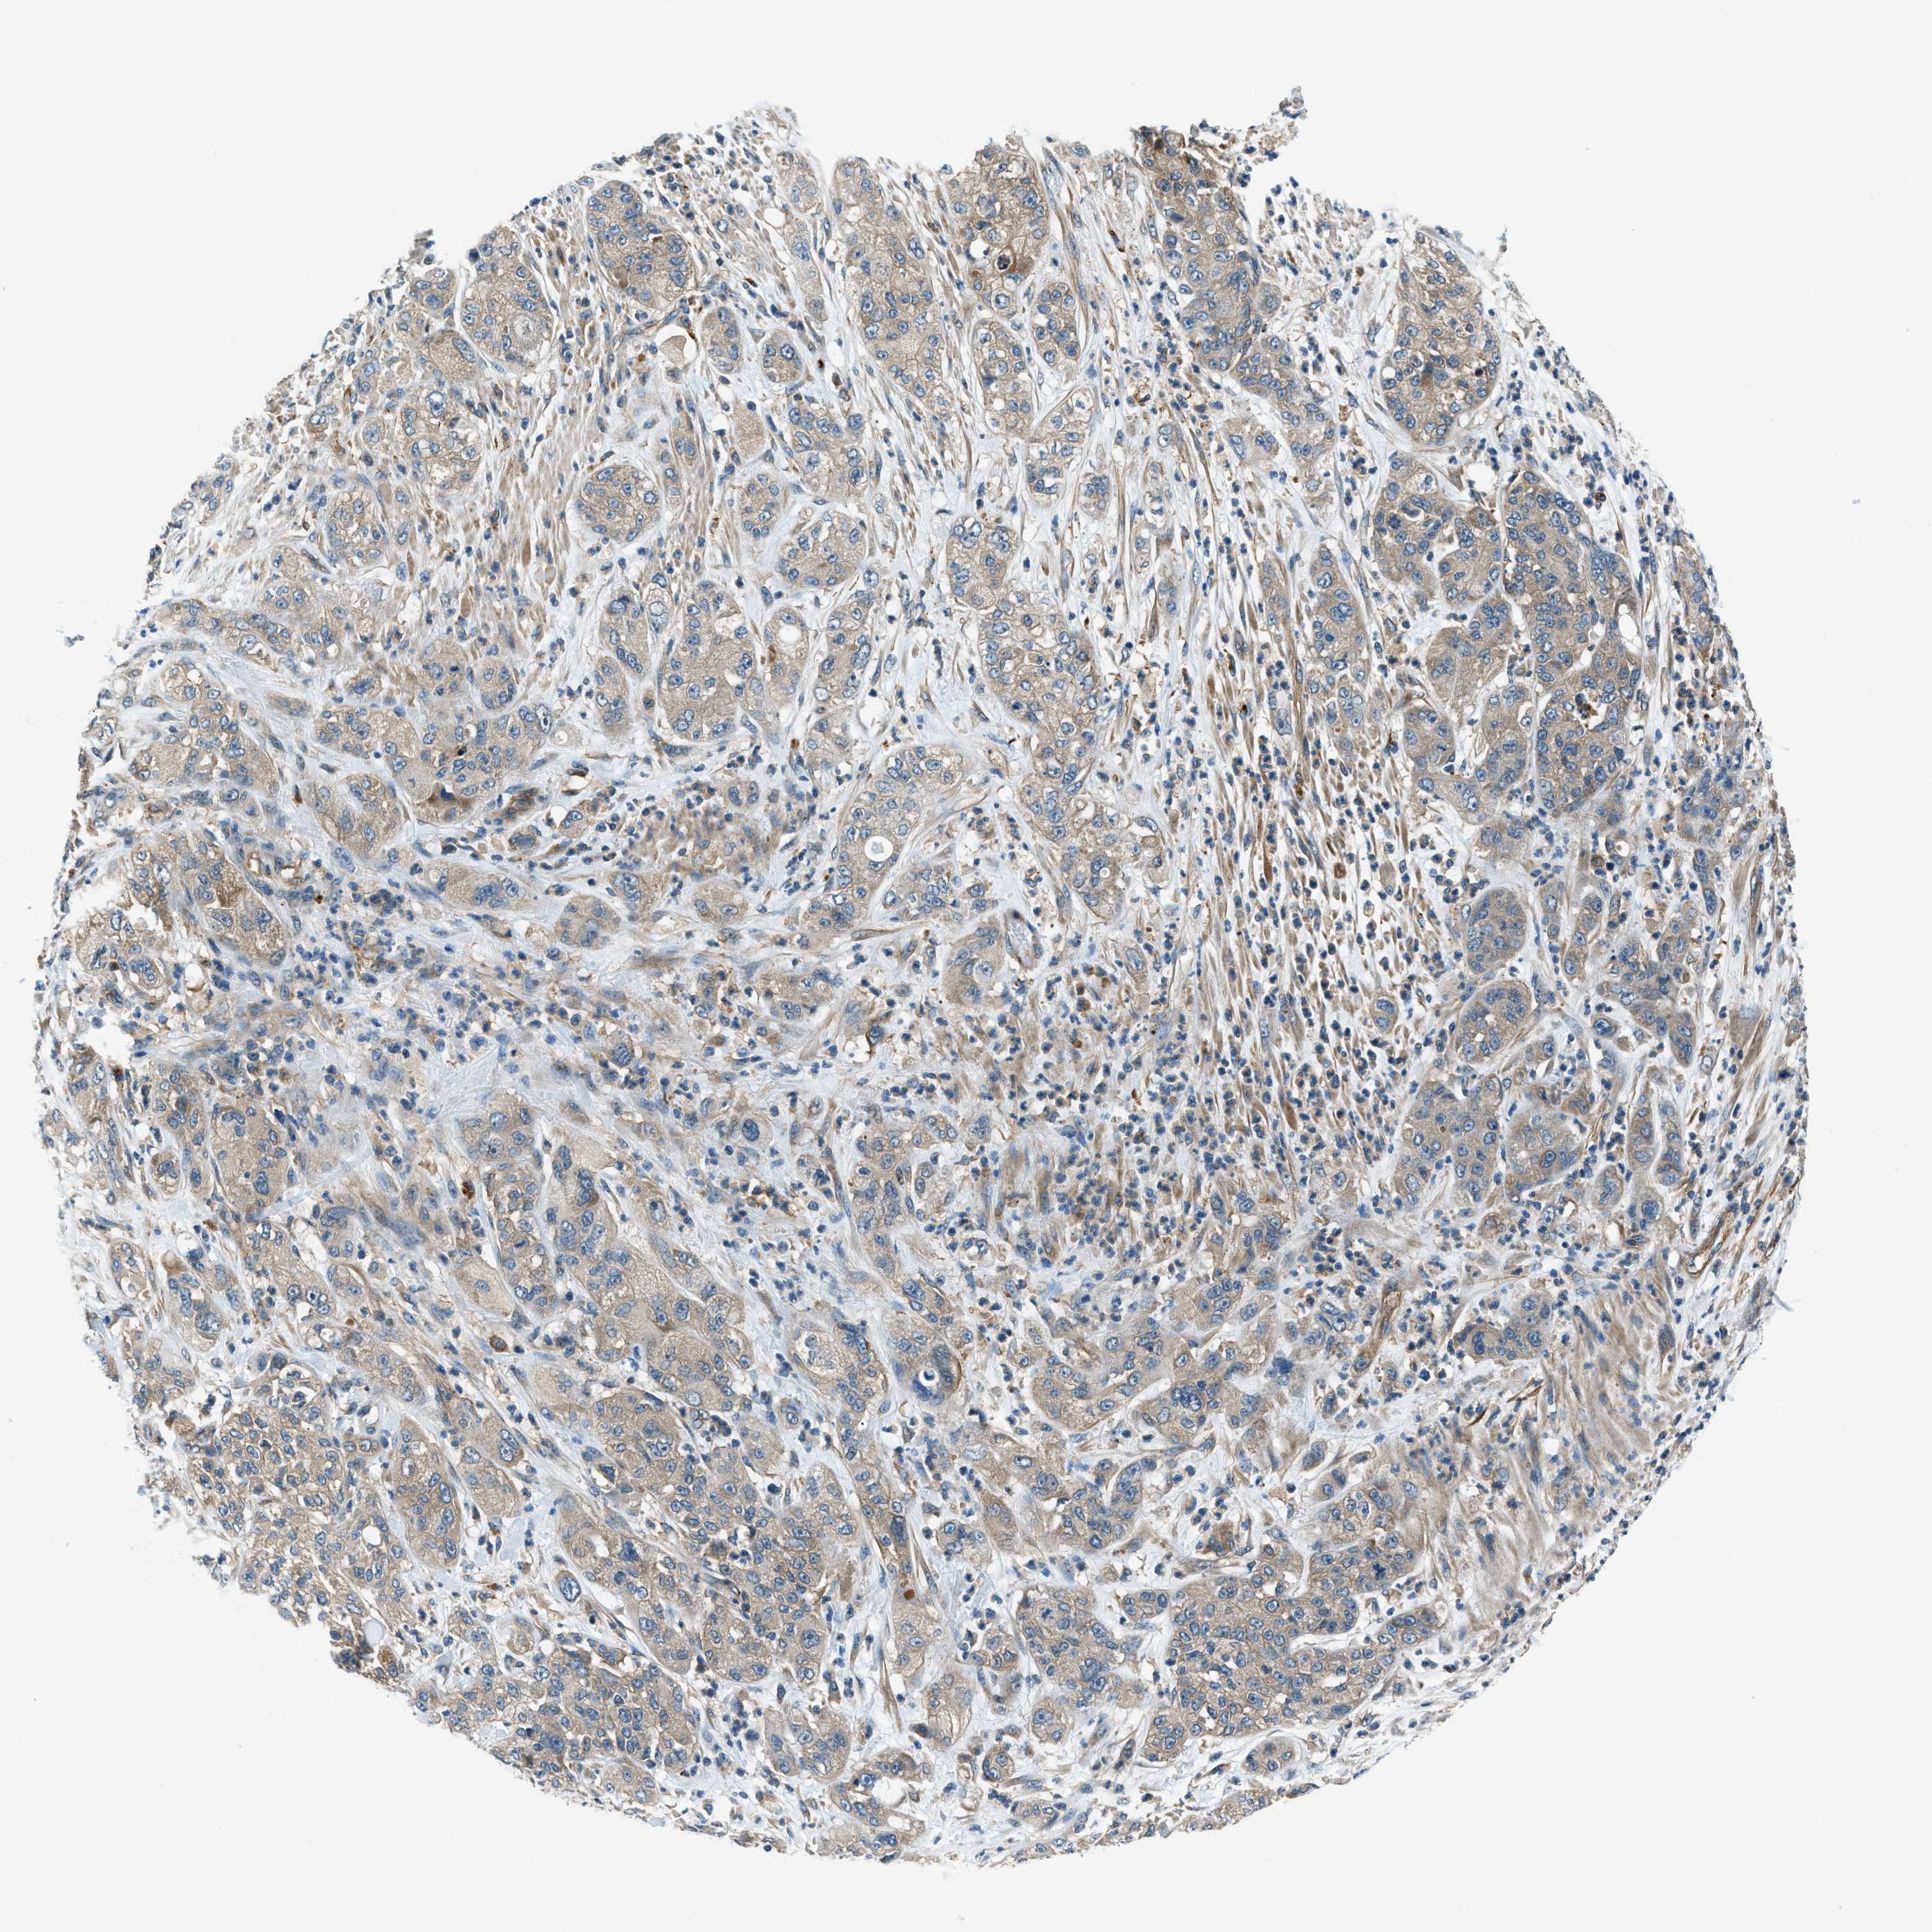

PANCREATIC CANCER - Protein expressioni

A mouse-over function shows sample information and annotation data. Click on an image to view it in a full screen mode. Samples can be filtered based on level of antibody staining by selecting one or several of the following categories: high, medium, low and not detected. The assay and annotation is described here.

Note that samples used for immunohistochemistry by the Human Protein Atlas do not correspond to samples in the TCGA dataset.

Antibody stainingi

Antibody staining in the annotated cell types in the current human tissue is reported as not detected, low, medium, or high, based on conventional immunohistochemistry profiling in selected tissues. This score is based on the combination of the staining intensity and fraction of stained cells.

Each image is clickable and will lead to virtual microscopy that enables deeper exploration of all samples and also displays staining intensity scores, fraction scores and subcellular localization as well as patient and tissue information for each sample.

Antibody HPA006119

Antibody HPA016599

Staining

High

Medium

Low

Not detected

Intensity

Strong

Moderate

Weak

Negative

Quantity

>75%

75%-25%

<25%

None

Location

Nuclear

Cytoplasmic/membranous

Cytoplasmic/membranous,nuclear

Adenocarcinoma, NOS

Adenocarcinoma, metastatic, NOS